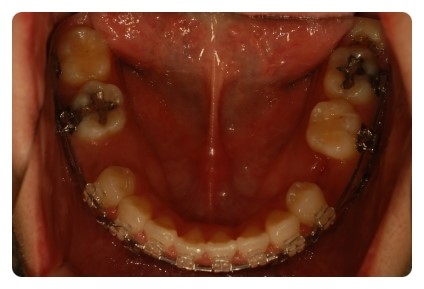

전 처음부터 발치를 안하고 유치를 잘라내가며 공간을 줄이는 중이엇는데

정면사진보니깐 왠지 교정 이제 마무리해도 될것같은데 ~~~ 사실 아직도 발치공간 마니 남앗어요

보통 발치를 할때 송곳니 바로 옆의 치아를 뽑는데 전 유치를 발치하는 경우라

그 뒤의 치아를 발치하기 때문에 발치공간이 하나도 보이지가 않아요 ㅋㅋ 좋은걸까요 ㅋㅋ